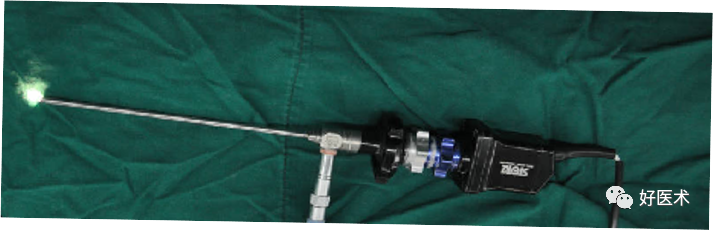

新的关节镜:Optec endoscopy Systems Gmbh采用新一代的OPTEC材料使关节镜具有一定的柔韧性,降低维修成本。

关节镜配套哪些关节镜技术速成诀窍_https://www.jmylbn.com_新闻资讯_第10张